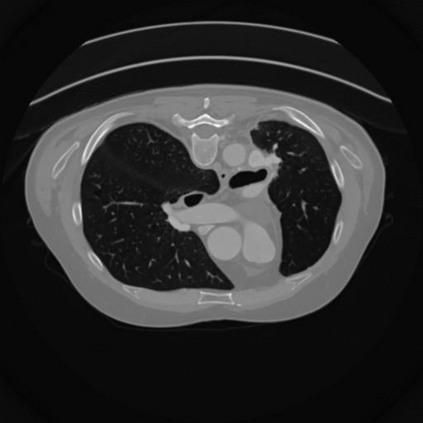

Sparse-view computed tomography (CT) -- using a small number of projections for tomographic reconstruction -- enables much lower radiation dose to patients and accelerated data acquisition. The reconstructed images, however, suffer from strong artifacts, greatly limiting their diagnostic value. Current trends for sparse-view CT turn to the raw data for better information recovery. The resultant dual-domain methods, nonetheless, suffer from secondary artifacts, especially in ultra-sparse view scenarios, and their generalization to other scanners/protocols is greatly limited. A crucial question arises: have the image post-processing methods reached the limit? Our answer is not yet. In this paper, we stick to image post-processing methods due to great flexibility and propose global representation (GloRe) distillation framework for sparse-view CT, termed GloReDi. First, we propose to learn GloRe with Fourier convolution, so each element in GloRe has an image-wide receptive field. Second, unlike methods that only use the full-view images for supervision, we propose to distill GloRe from intermediate-view reconstructed images that are readily available but not explored in previous literature. The success of GloRe distillation is attributed to two key components: representation directional distillation to align the GloRe directions, and band-pass-specific contrastive distillation to gain clinically important details. Extensive experiments demonstrate the superiority of the proposed GloReDi over the state-of-the-art methods, including dual-domain ones. The source code is available at https://github.com/longzilicart/GloReDi.